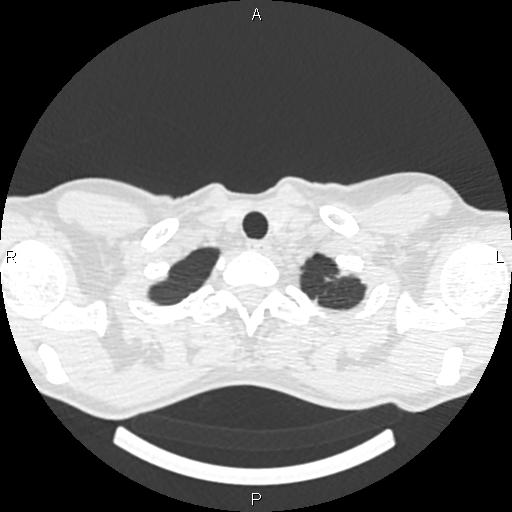

Женщина, 1975 г.р. ВИЧ инфицирована. Жалобы неспецифичны: легкое покашливание (иногда), легкое похудение. Температуры нет. Первое КТ сделано ровно 4 мес назад. Отмечались множественные...

Тип: Клиническое наблюдение

Область: Грудная клетка и верхние дыхательные пути

Модальность: КТ

Дата: 01.06.2016 - 20:47